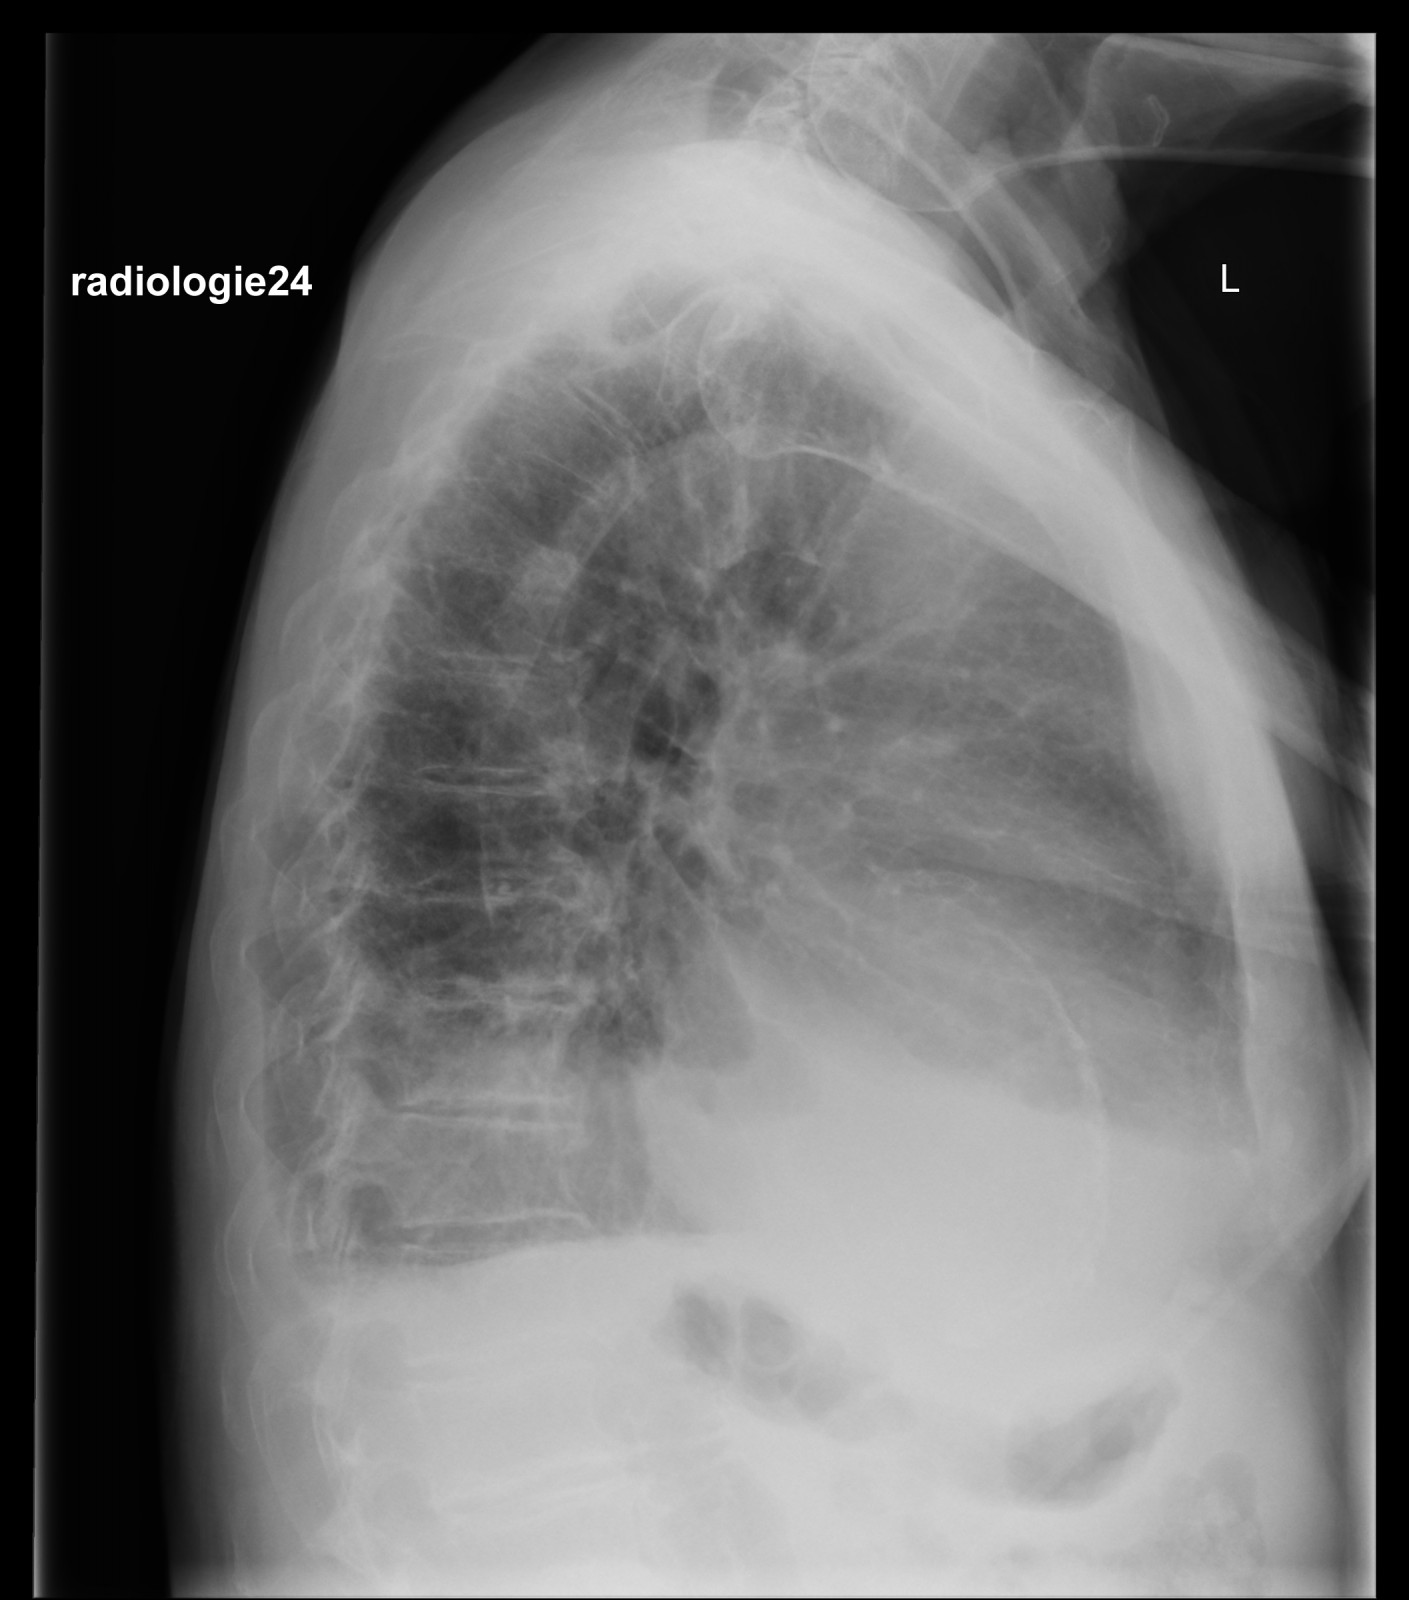

Röntgenfall des Monats Februar 2018 mit Auflösung

75 jähriger Patient

Zunehmende Belastungsdyspnoe.

Ihre Diagnose? Nebenbefunde?